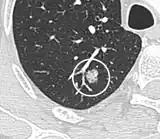

- Margin morphology: a spiculated margin is a risk factor for cancer.[8] Benign causes tend to have a well defined border, whereas lobulated lesions or those with an irregular margin extending into the neighbouring tissue tend to be malignant.[10] In particular, spiculations are highly predictive of malignancy with a positive predictive value up to 90%.[9] Also, a "notch sign", which is an abrupt indentation of the nodule, increases the risk of cancer, but may also be found in granulomatous diseases.[9]

- Round well-delineated solid lung nodule with smooth border.[9]

- Lobulated nodule.[9]

- Spiculated lung nodule.[9]

- A "notch sign".[9]

- A triangular perifissural node can be diagnosed as a benign lymph node.[9]